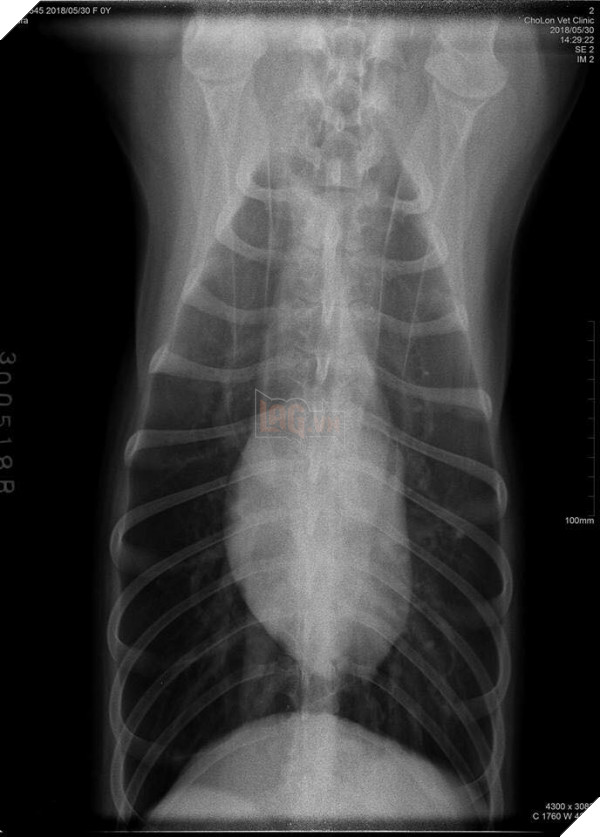

Về phía con Sen tội nghiệp, sau giây phút bàng hoàng, vội vã sờ nắn rồi tức tốc đưa đi bệnh viện, chụp chiếu mất 700.000 ngàn, và may thay  “nó chẳng sao cả, xương không gãy cái nào, chỉ bị sung huyết thùy đỉnh phổi và có dịch”. Thật là một cái kết quá có hậu cho “thanh niên ngáo” tìm đến cách nhảy lầu để trốn đi chơi.